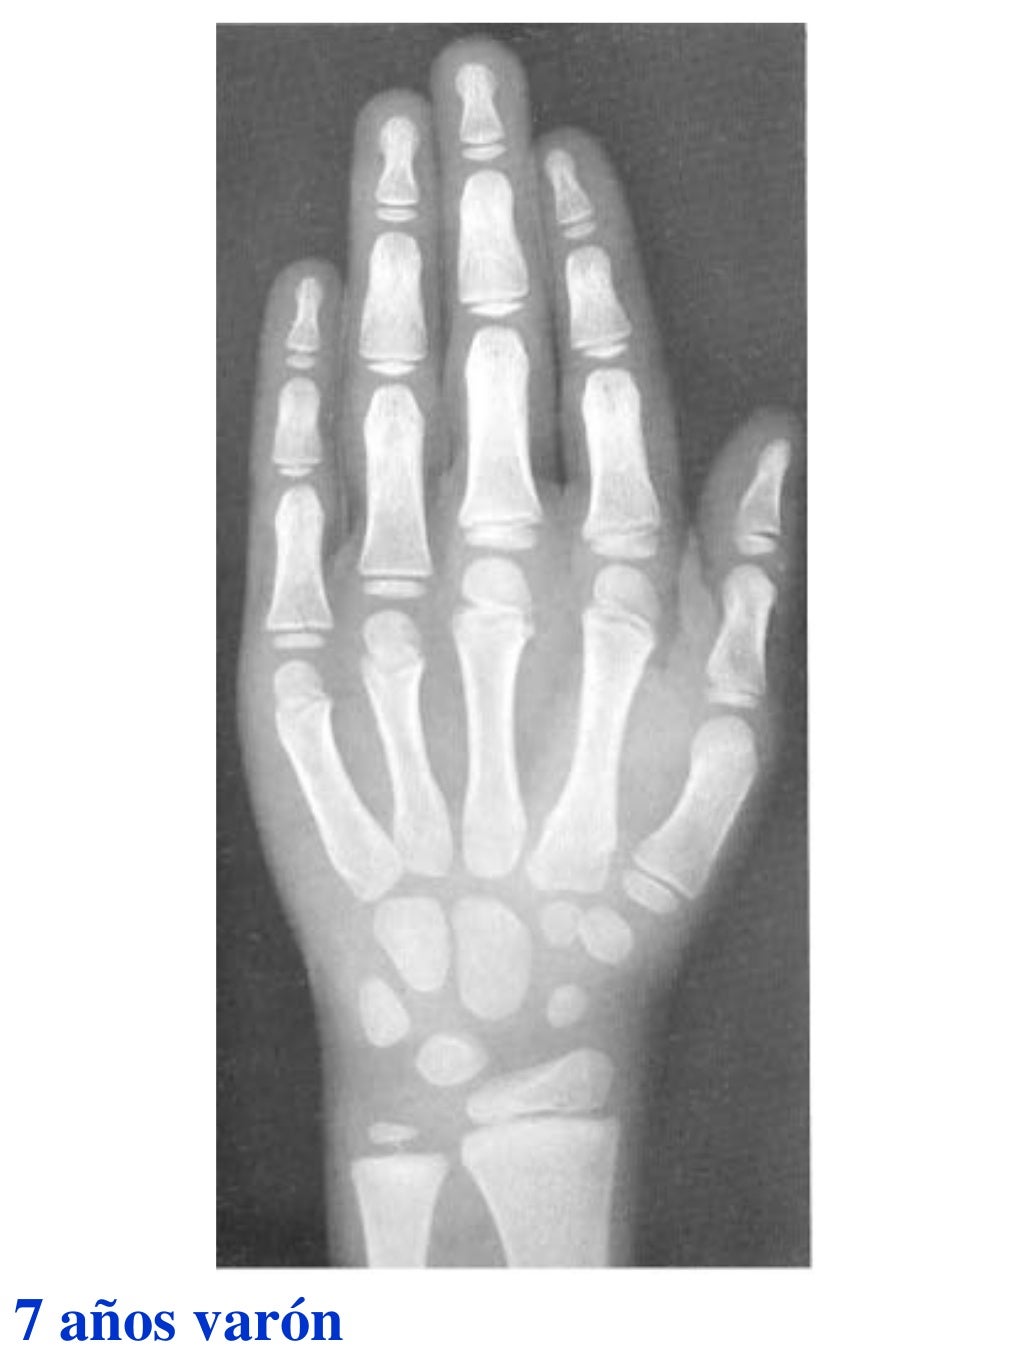

Figura 2 Imágenes de radiografías de mano y muñeca izquierda del

Figura 2 Imágenes de radiografías de mano y muñeca izquierda del Tablas De Greulich Y Pyle Edad Osea The greulich and pyle atlas is used to estimate the age of children and adolescents. El método de greulich y pyle(1) es un método simple de valoración de la edad ósea en pacientes pediátricos. El diagnóstico y la clasificación se basan en el examen físico, el análisis del crecimiento, la maduración ósea, la ecografía de útero y gónadas, y los. Tablas De Greulich Y Pyle Edad Osea.